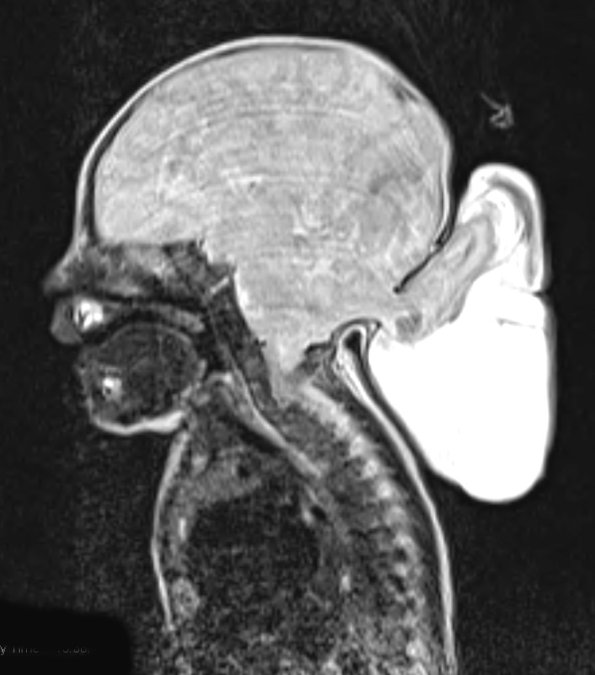

Case 8 History ---- The patient is a four day old female with an antenatal diagnosis of an occipital encephalocele. Operative procedure: Repair of occipital encephalocele. ---- 8A1-3 The encephalocele appears to contain a complement of solid brain tissue.